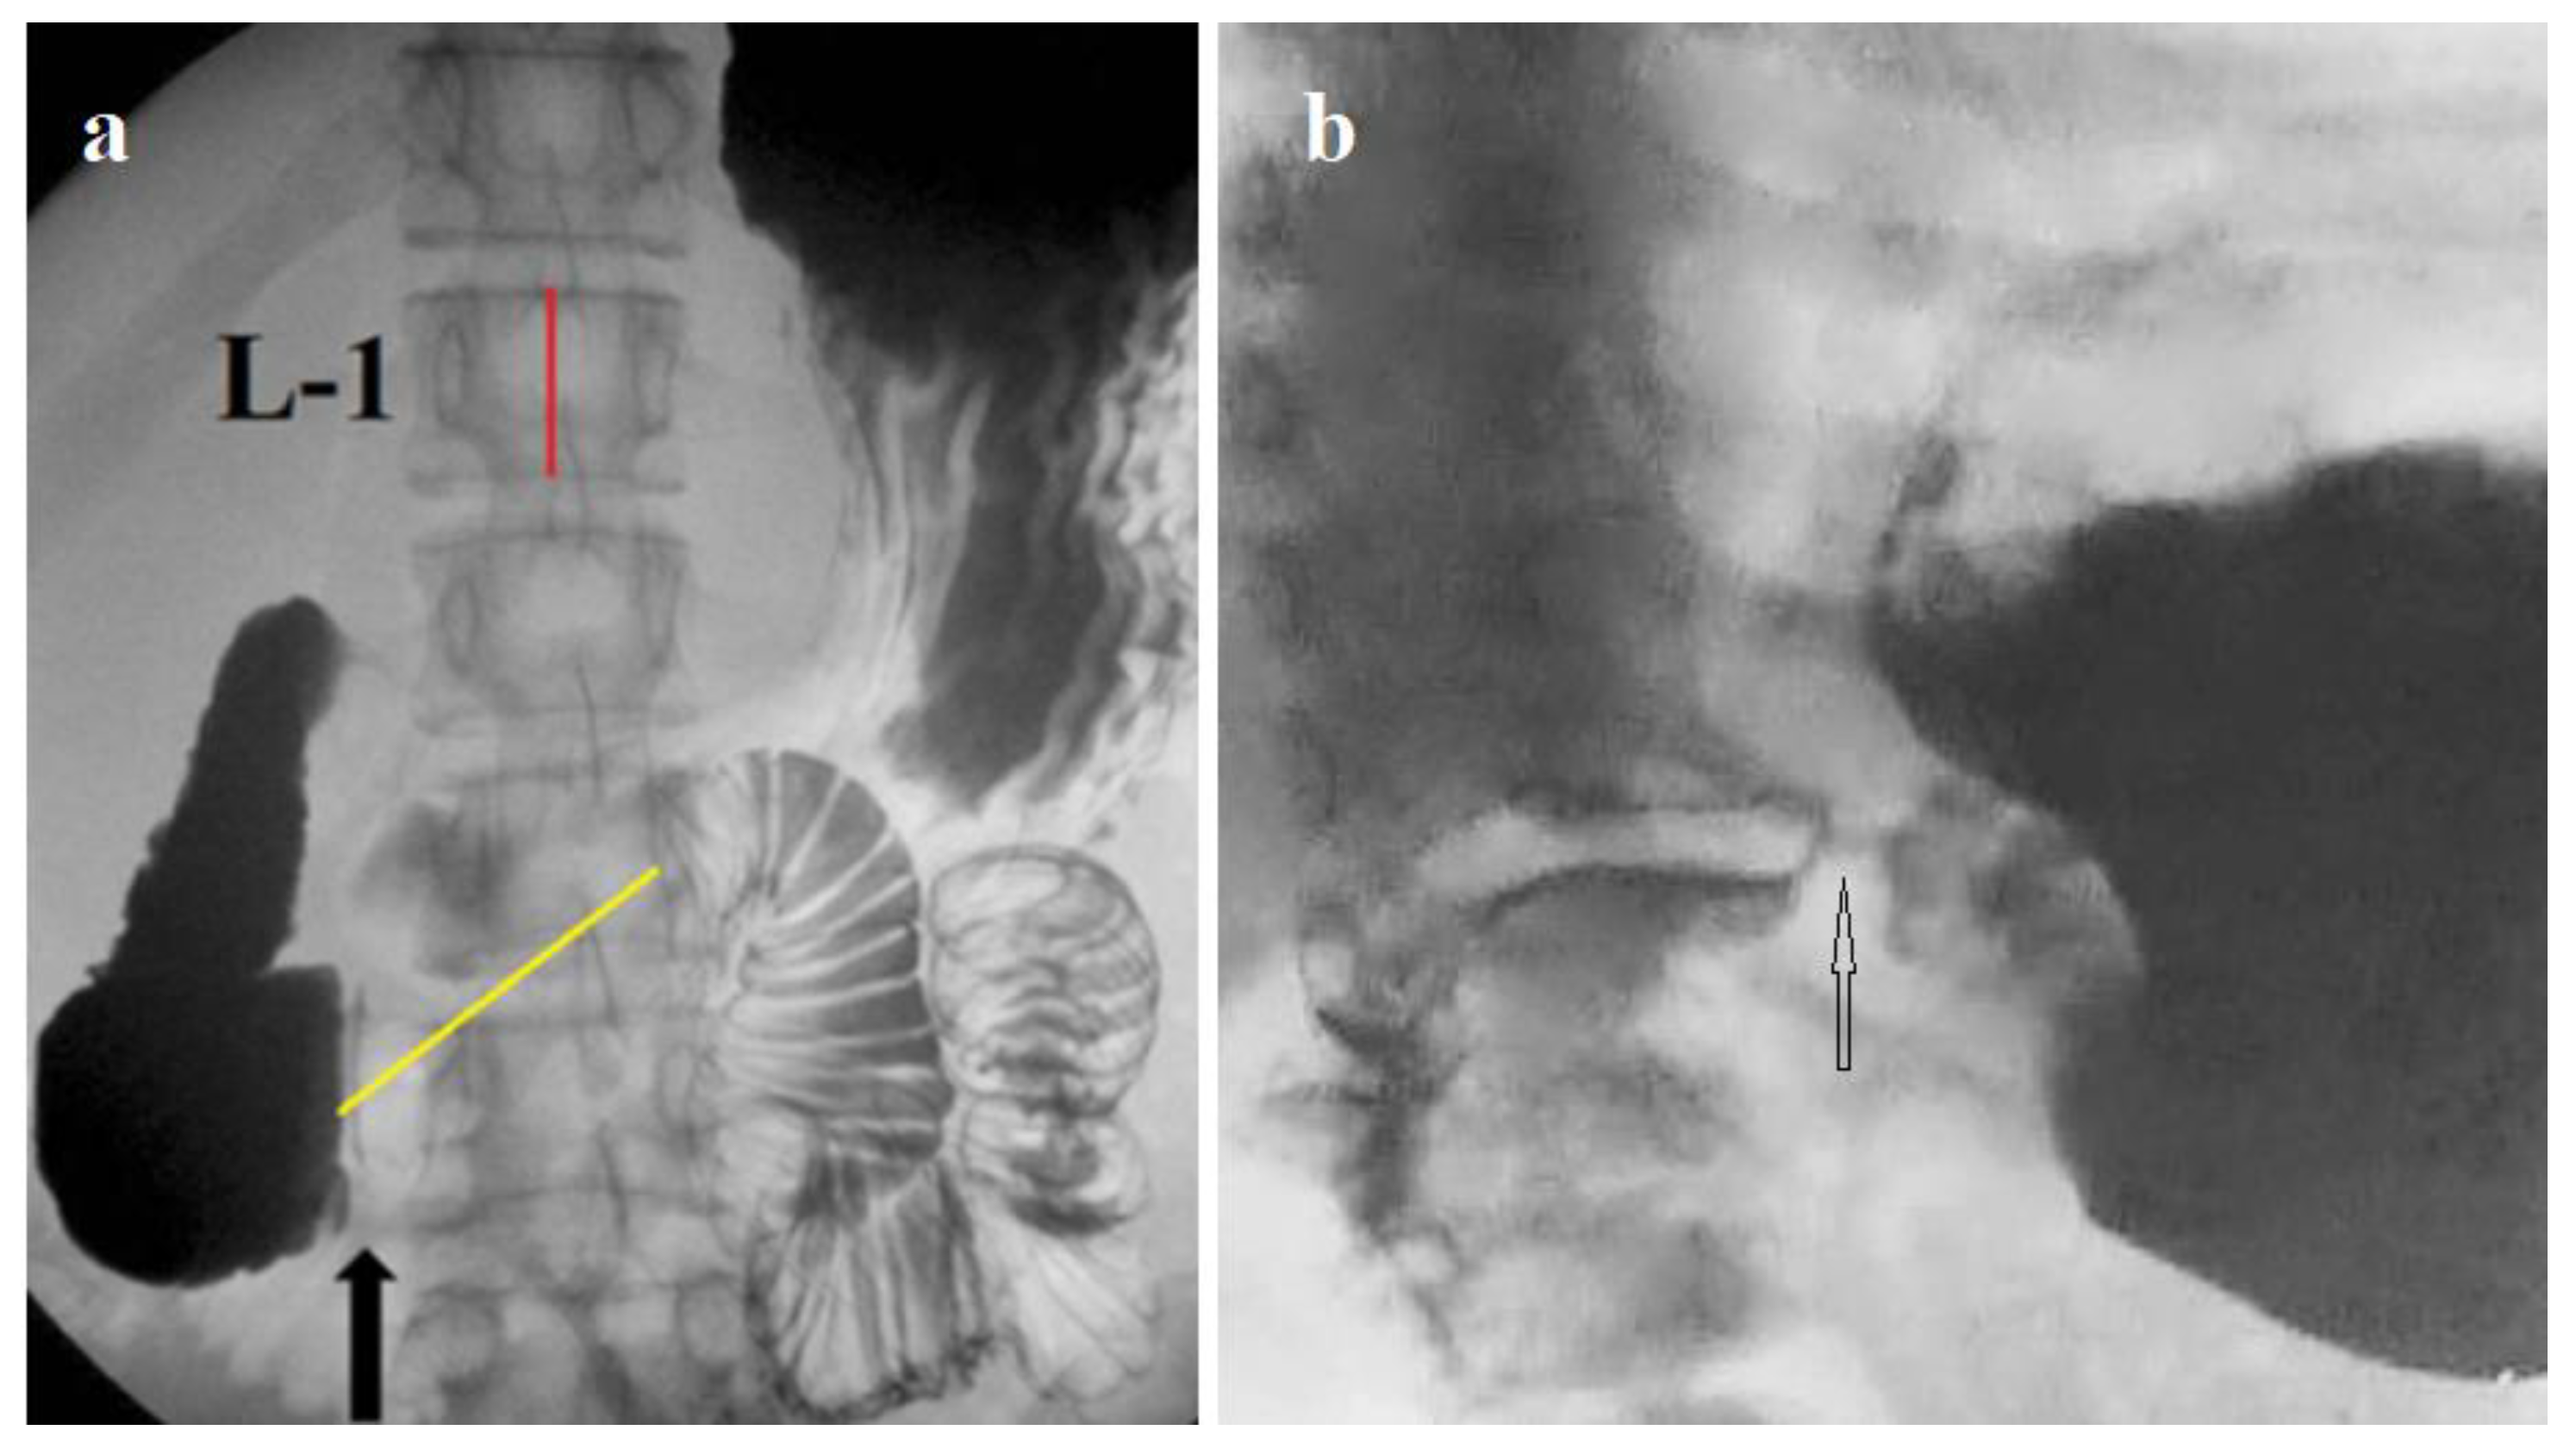

- A small gas bubble in the stomach is caused by shortening and weakness of the LES, which can be used for screening of gastroesophageal reflux disease [49].

- Levin MD, Jin IG. Screening of gastroesophageal reflux disease based on the size of the gastric gas bubble. Eksp Klin Gastroenterol. 2018; 152(4):23-9.